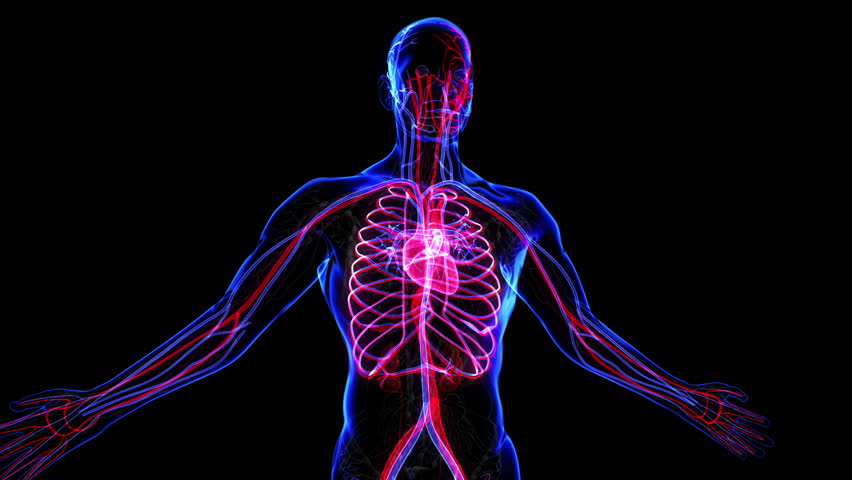

Of the figure.certain to become the standard reference in the field, human anatomy for artists will be in. It is the most complete reference of human anatomy available on web, ipad, iphone explore over 6700 anatomic structures and more than 670 000 translated medical labels. Also known as an anomaly scan or anatomic survey, an anatomy scan is the most extensive ultrasound exam carried out on the fetus during for example, if the baby has a heart defect, being born in a hospital staffed with pediatric cardiologists can mean the difference between life and death. It is my awesome anatomy anki deck.